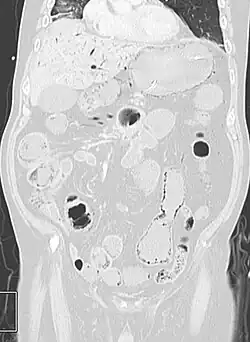

Pneumatosis intestinalis at computed tomography in intestinal ischemia. Lung window for better representation of the gas deposits in the intestinal walls. Coronal reconstruction. -

Pneumatosis intestinalis in the coronal computed tomography in lung window. It can be seen next to gas entrapment in the bowel wall and gas in the stomach wall and in numerous vessels, including the portal vein into the liver. -